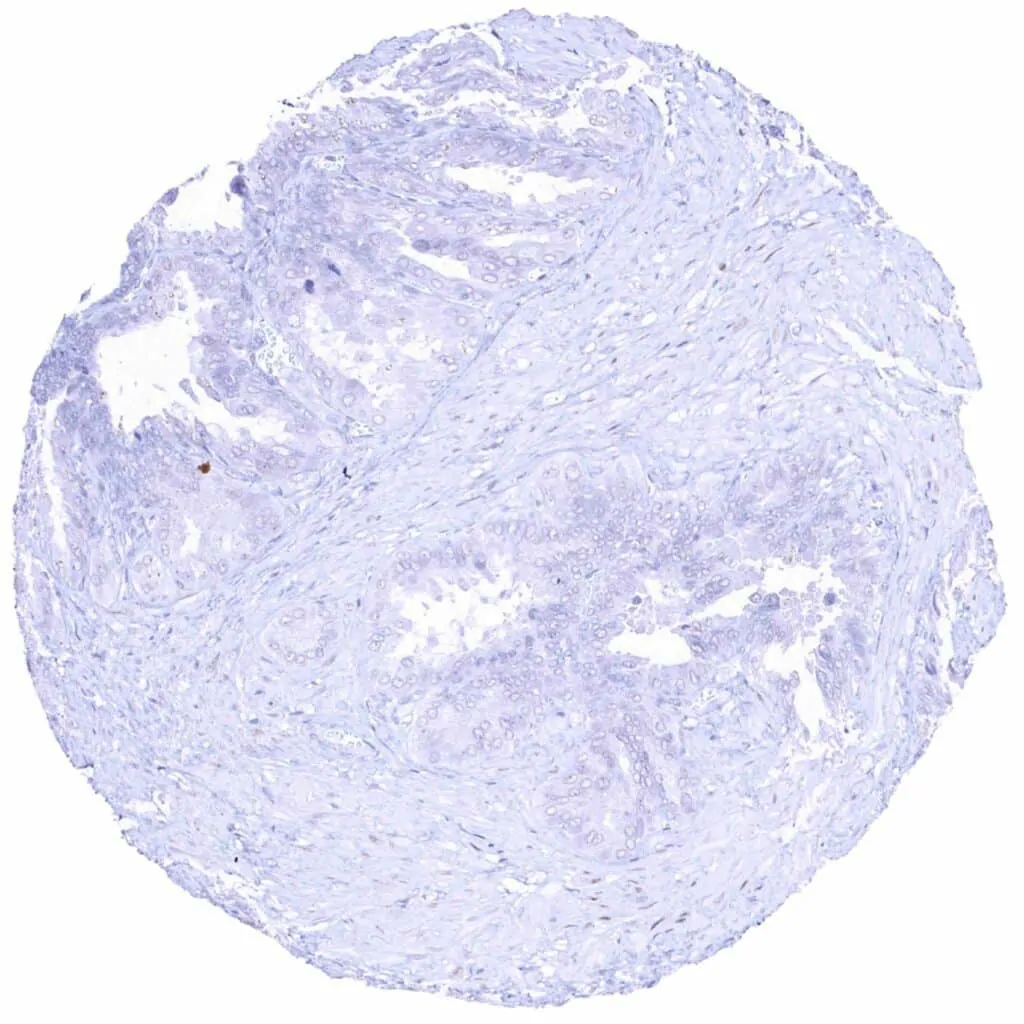

Prostate